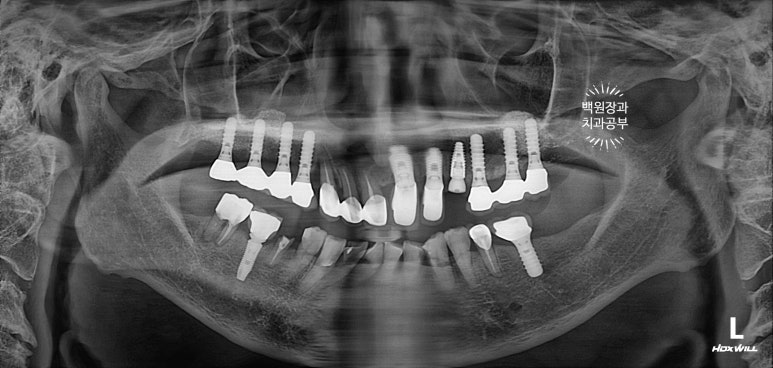

잘 보시면, 임플란트가 총 위턱에 9개, 아래턱에 2개 되어있는데 대부분이 아주 유명한 외국 임플란트 제품들입니다. 특히나 위턱 어금니는 스트라우만 standard 제품으로, 제가 가장 신뢰하는 제품 중 하나입니다.

무려 20년이 넘으셨다고 했는데... 임플란트 주위염 하나 없이 너무너무 잘 사용하고 계시더라구요.

처음 오셨을 때, 치과용 파노라마 사진에서 파란색 화살표로 표시해둔 두 치아 - 왼쪽 위 송곳니와 오른쪽 아래 작은어금니가 뿌리만 남아있는 상태로 내원하셨어요.

특이할만한 점이, 두 치아 모두 신경치료와 크라운 치료를 받았던 치아였다는 것... 역시나 신경치료는 치아 건강에 그리 좋지 않음을 알 수 있습니다..

아까 말씀드렸듯, 왼쪽 위 송곳니와 오른쪽 아래 작은어금니에 뿌리만 있는 잔존치근이 관찰됩니다.